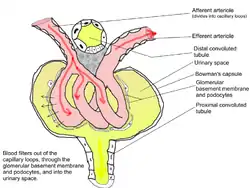

The renal corpuscle is the site of the filtration of blood plasma. The renal corpuscle consists of the glomerulus, and the glomerular capsule or Bowman's capsule.[3]: 1027

The renal corpuscle has two poles: a vascular pole and a tubular pole.[4]: 397 The arterioles from the renal circulation enter and leave the glomerulus at the vascular pole. The glomerular filtrate leaves the Bowman's capsule at the renal tubule at the urinary pole.

Glomerulus

The glomerulus is the network known as a tuft, of filtering capillaries located at the vascular pole of the renal corpuscle in Bowman's capsule. Each glomerulus receives its blood supply from an afferent arteriole of the renal circulation. The glomerular blood pressure provides the driving force for water and solutes to be filtered out of the blood plasma, and into the interior of Bowman's capsule, called Bowman's space.

Only about a fifth of the plasma is filtered in the glomerulus. The rest passes into an efferent arteriole. The diameter of the efferent arteriole is smaller than that of the afferent, and this difference increases the hydrostatic pressure in the glomerulus.

Bowman's capsule

The Bowman's capsule, also called the glomerular capsule, surrounds the glomerulus. It is composed of a visceral inner layer formed by specialized cells called podocytes, and a parietal outer layer composed of simple squamous epithelium. Fluids from blood in the glomerulus are ultrafiltered through several layers, resulting in what is known as the filtrate.

The filtrate next moves to the renal tubule, where it is further processed to form urine. The different stages of this fluid are collectively known as the tubular fluid.

The nephron is the minute or microscopic structural and functional unit of the kidney. It is composed of a renal corpuscle and a renal tubule. The renal corpuscle consists of a tuft of capillaries called a glomerulus and a cup-shaped structure called Bowman's capsule. The renal tubule extends from the capsule. The capsule and tubule are connected and are composed of epithelial cells with a lumen. A healthy adult has 1 to 1.5 million nephrons in each kidney.[1]: 22 Blood is filtered as it passes through three layers: the endothelial cells of the capillary wall, its basement membrane, and between the foot processes of the podocytes of the lining of the capsule. The tubule has adjacent peritubular capillaries that run between the descending and ascending portions of the tubule. As the fluid from the capsule flows down into the tubule, it is processed by the epithelial cells lining the tubule: water is reabsorbed and substances are exchanged (some are added, others are removed); first with the interstitial fluid outside the tubules, and then into the plasma in the adjacent peritubular capillaries through the endothelial cells lining that capillary. This process regulates the volume of body fluid as well as levels of many body substances. At the end of the tubule, the remaining fluid—urine—exits: it is composed of water, metabolic waste, and toxins.

The interior of Bowman's capsule, called Bowman's space, collects the filtrate from the filtering capillaries of the glomerular tuft, which also contains mesangial cells supporting these capillaries. These components function as the filtration unit and make up the renal corpuscle. The filtering structure (glomerular filtration barrier) has three layers composed of endothelial cells, a basement membrane, and podocytes (foot processes). The tubule has five anatomically and functionally different parts: the proximal tubule, which has a convoluted section the proximal convoluted tubule followed by a straight section (proximal straight tubule); the loop of Henle, which has two parts, the descending loop of Henle ("descending loop") and the ascending loop of Henle ("ascending loop"); the distal convoluted tubule ("distal loop"); the connecting tubule, and the last part of nephron the collecting ducts. Nephrons have two lengths with different urine-concentrating capacities: long juxtamedullary nephrons and short cortical nephrons.